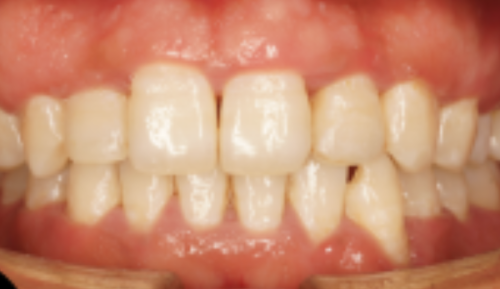

无论是常见的牙齿清洁、补牙,还是复杂的牙齿矫正、种植牙手术,齐美口腔的医生们都能游刃有余地应对。他们紧跟口腔医学的发展趋势,不断学习和掌握全新的治疗技术,为患者提供良好质的口腔医疗服务。有了这样专精的医生团队,你还会担心看牙的成效吗?